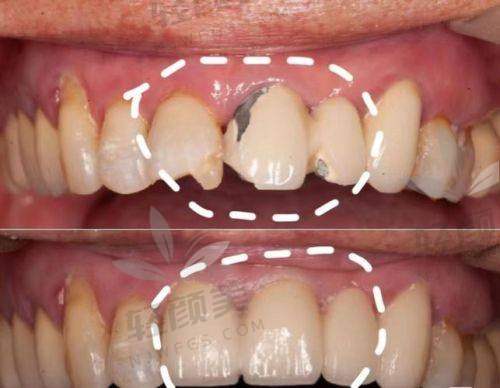

通俗点说,烤瓷牙=外表好看+内心强悍。它是一种戴在打磨过的牙齿上的牙冠,底下是金属或氧化锆、玻璃陶瓷,上面包着一层陶瓷。功能上,它既能弥补蛀牙、裂牙、缺失,也能改善牙齿颜色和形态。比树脂补牙更结实,同时容貌还在线,拍照都能看到牙齿在发光✨。

前牙颗颗上镜,后牙天天受虐,怎么选烤瓷牙得看你的主要用途——

✅前牙修复:建议选E-MAX、泽康、威兰德这种“容貌担当”,透明度高,贴着真牙容貌拉满。